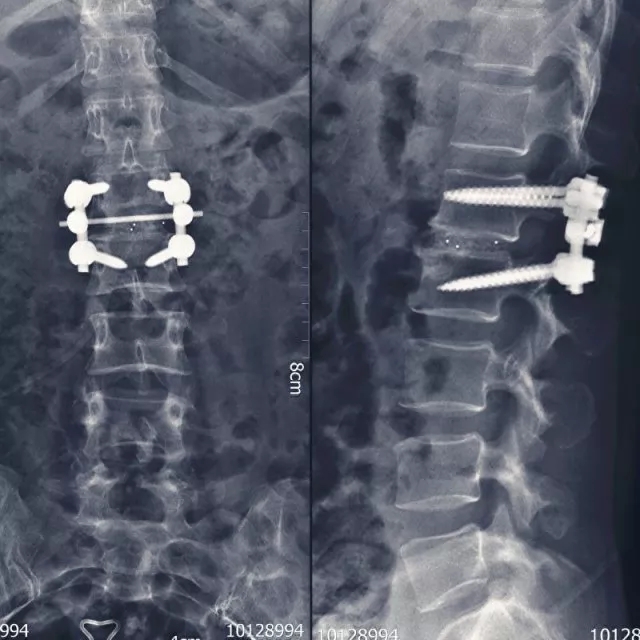

? 术后内固定状态

入院时,患者卧床不能自理,双下肢剧烈疼痛让患者连续几个晚上睡觉都十分困难。查体显示双侧髂腰肌肌力II级,双侧股四头肌力III级,远端肌力轻度减低。鞍区感觉减退,肛门括约肌轻度松弛,小便费力。综合影像学检查结果诊断为腰1/2椎间盘脱出,马尾综合症。6月25日,在空军军医大学西京医院脊柱外科王哲主任安排下,丁坦副教授主刀实施腰1/2椎板切除减压,髓核摘除,椎间植骨融合内固定术,手术用时2小时顺利结束。

术后,患者剧痛很快消失,在植入式生物激光脊神经治疗仪的治疗下神经功能较快恢复,7月2日,术后7天出院时,患者双下肢髂腰肌肌力由术前II级恢复到IV+级,双侧股四头肌力由III级恢复到V级,可以正常行走,大小便恢复正常。